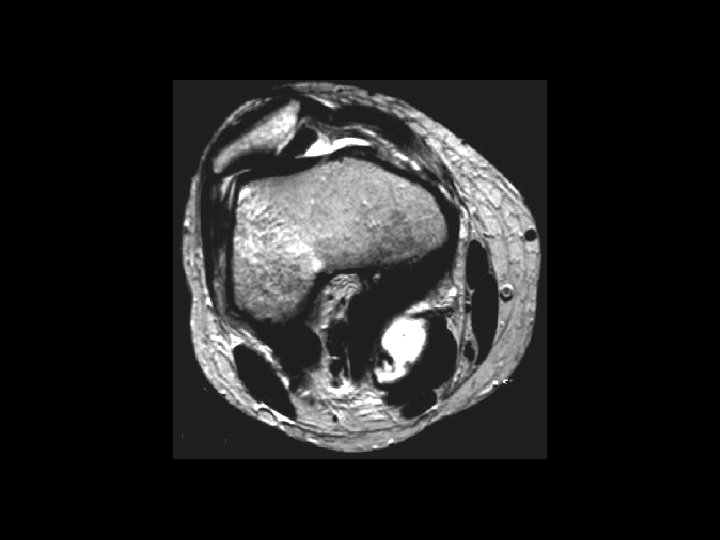

Synovial Osteochondromatosis